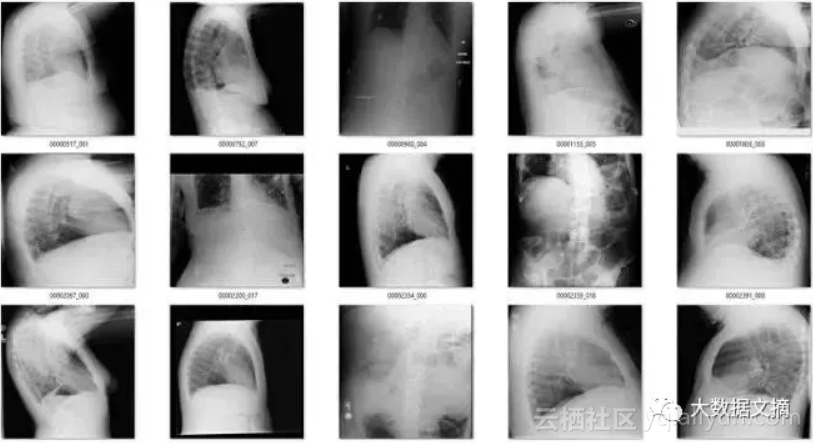

该模型一共标记出了171个“旋转”的图像。有趣的是,它实际上作为一个“异常”检测器,识别出许多在非胸部X光的图像。这也不难理解,因为这个模型可能是在学习解剖学的标志。任何异常的东西,如旋转的图像或者是其他身体部位的X射线图像,都不具有正常图片应有的特征。真是意外收获!

在余下的120个图像中,56个并不是正面胸片。其中主要包括了侧面胸片和腹部X光片,这也是我想要清理出去的异常图片。

即使是很少量的带标签的数据都很有帮助。我用旋转检测器检测到的侧面和错误区域的X光图(n=56张)训练了一个新的模型。

结果很好!新的模型帮我找到了几百张侧面,腹部和骨盆X光图。